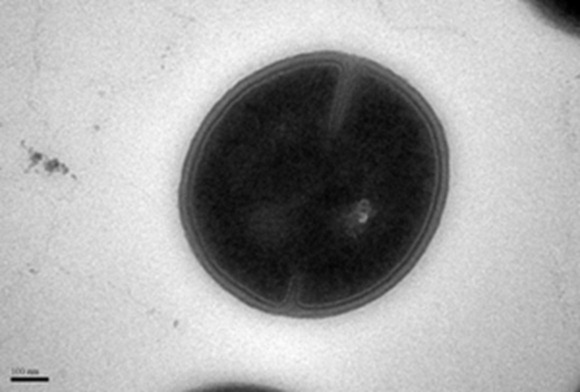

Figure 1: Transmission Electron Microscope (TEM) image of the MRSA cell before treatment.